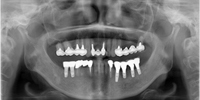

失われた歯の数、インプラントを埋め込む歯の硬さ、大きさ、位置により、治療にはさまざまな選択肢があります。

歯にかかる力の方向や強さはもちろん、患者さんに無理のない衛生管理などを含め総合的に検討した上で、治療計画が立てられます。

顎の骨にインプラントを埋め込みます。

一次手術後、3~6ヵ月の治癒期間をおく事で、インプラントと骨が強い力で結合します(オッセオインテグレーションといいます)。